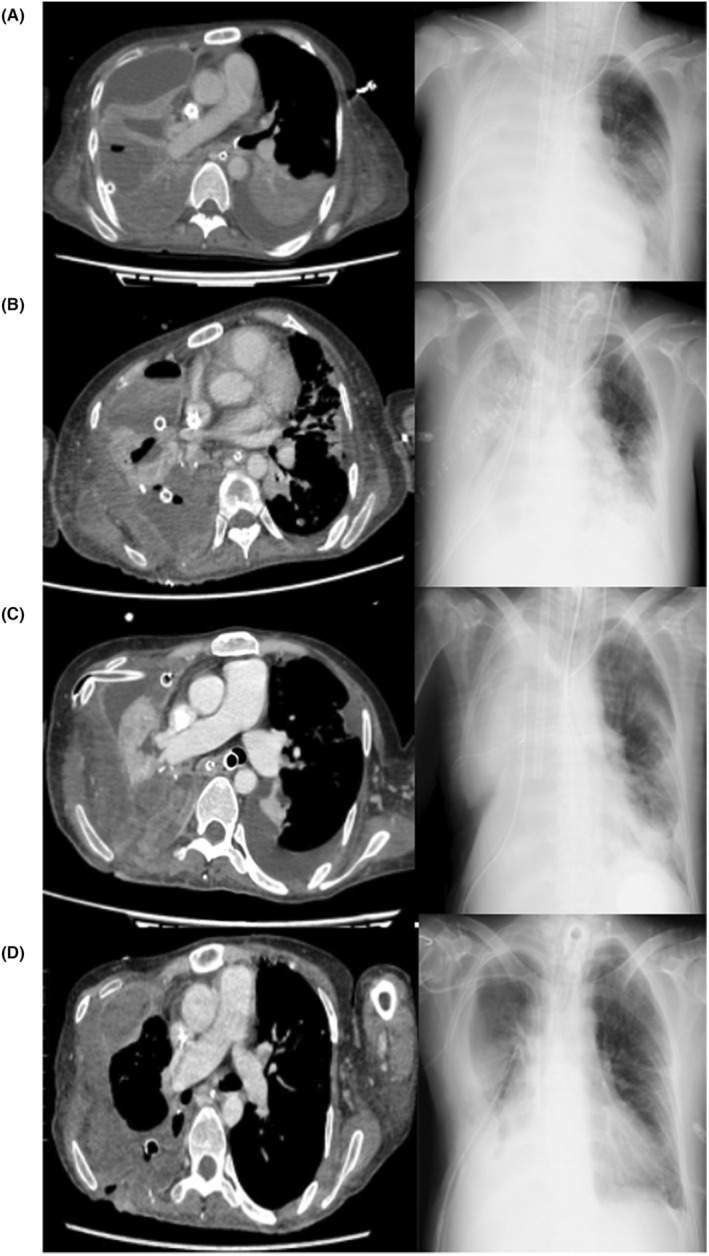

FIGURE 2.

The transition of chest computed tomography (CT) and chest X‐ray. (A) Day 4. We confirmed the characteristics of the lung abscess. As intercurrent air leakage was present, we decided to perform thoracic surgery. (B) Day 17/18. Chest CT was performed on Day 17, and chest X‐ray on Day 18. On Day 17, we performed CT because the circulatory dynamics were unstable and we suspected sepsis. On the same day, re‐thoracotomy was performed. (C) Day 27. The right lung was pale in appearance. On Day 32, independent lung ventilation (ILV) was again started for the purpose of physiological lung separation. After that, transparency of the right lung gradually improved. (D) Day 56. Veno‐venous extracorporeal membrane oxygenation was decannulated on Day 48. Transparency of the right lung improved.